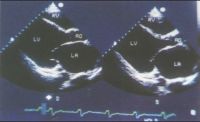

3.超声心动图:在本病早期即可见到心腔轻度扩大,尤其左心室,室壁运动减弱,后期各心腔均扩大,室间隔与左室后壁运动也减弱。二尖瓣前叶双峰可消失而前后叶呈异向活动。左室喷血比数常减至50%以下,心肌缩短比数也减小。可能有少量心包积液。

扩张型心肌病超声心动图表现